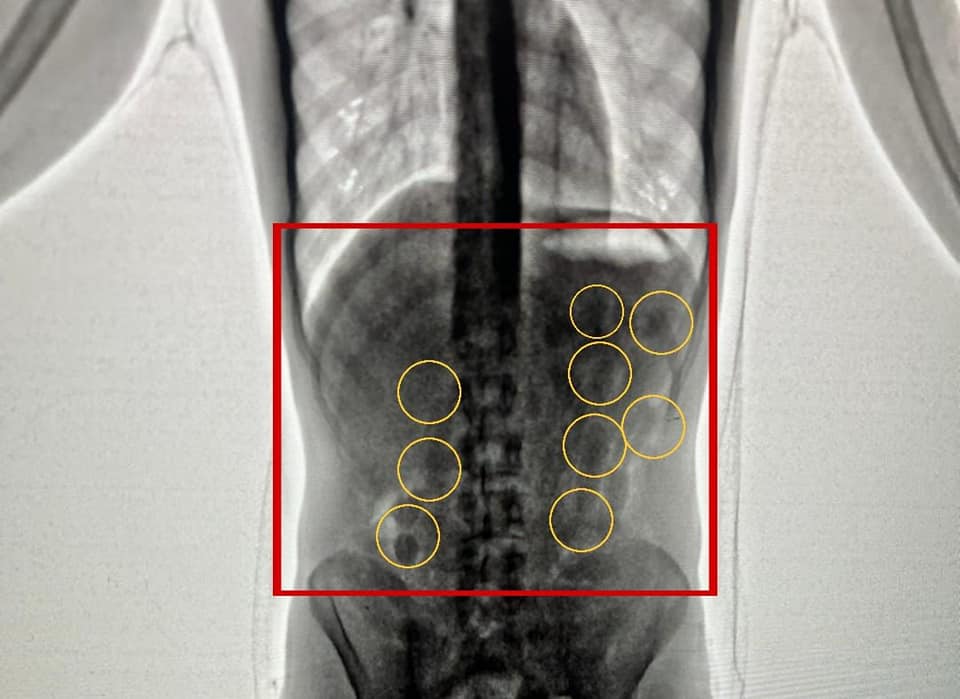

Amman – AND foils the smuggling of huge quantity of drugs that were on their way to a neighboring country, and arrested members of two gangs connected to regional drug smuggling gangs.

The destruction of these drugs comes as an extension of the qualitative operational efforts made by the Anti-narcotics

Today, Public Security Directorate, represented by the Anti-Narcotics Department, destroyed large quantities of narcotic drugs, seized in (33) cases whose rulings were final.

As part of the efforts made by the Public Security Directorate to combat the scourge of drugs by all means, and the PSD

Anti-Narcotics Department destroyed quantities of narcotics that were seized in (1045) cases which was varied between trafficking to possession and smuggling.